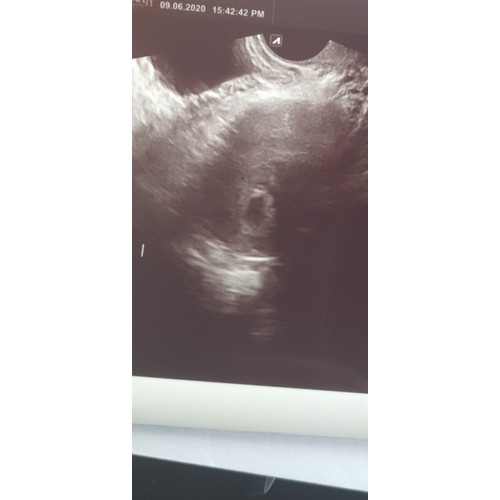

maar je heb wel een ringgg erin mischien is je baby toch iets kleiner ik had het ook kijk later kwam er een ringetje in wat jij heb op je echo fototje, 1 week later zag je me baby🥰

Ik dacht op deze 2e foto ook een ringetje te zien!! Zie jij het ook? Rechts onder? We houden hoop 🤞🏻🍀🙏🏼